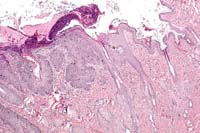

Case 29-1. Skin. Pigmented keratin is distending and distorting hair follicles. The epidermis is also hyperpigmented. The follicles are slanted and the errector pili muscles are parallel to the skin surface. 10X

AFIP Diagnosis: Haired skin: Dysplasia, adnexal, with epidermal and follicular orthokeratotic hyperkeratosis, hyperpigmentation, pigmentary incontinence, and follicular dilatation, Chinese Crested, canine.

Conference Note: Additional histologic features of this interesting case were discussed in conference. These include:

a. Arrector pili muscles are often oriented parallel to the skin surface.

b. Apocrine ducts sometimes enter follicles at abnormal locations.

c. Mesenchymal cells of the dermal papillae occasionally surround the epidermal bulb, rather than forming a bulb- or cone-shaped projection surrounded by the hair bulb epidermis.

d. There is remarkable comedo formation.

There is moderate to severe orthokeratotic hyperkeratosis, which extends into the follicular infundibulum with dilation of the follicular ostium. A few catagen and telogen follicles can still be found. The follicular papillum can be identified in abnormal locations, such as adjacent to the sebaceous ducts and at the base of follicles showing severe follicular dilation secondary to keratin accumulation. Some of the hairs are found at very unusual angles. Occasional melanophages are present in the dermis. The sebaceous glands and apocrine glands are within normal limits.